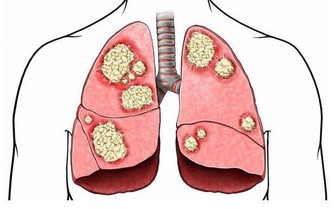

5. 更容易罹患致命疾病

如果你長期晚睡,身體會分泌更多的皮質醇激素,這種激素在壓力狀態下可以保命。比如看到老虎我們拔腿就跑,而且跑得飛快,這是皮質醇的功勞。但皮質醇水平長期偏高,意味著你的血壓、血糖可能升高,更容易出現高血壓、糖尿病甚至癌症等,對心臟健康也非常不利。所以,那些早睡的人,出現動脈硬化的風險要比晚睡者小,而且更不容易被猝死找上。